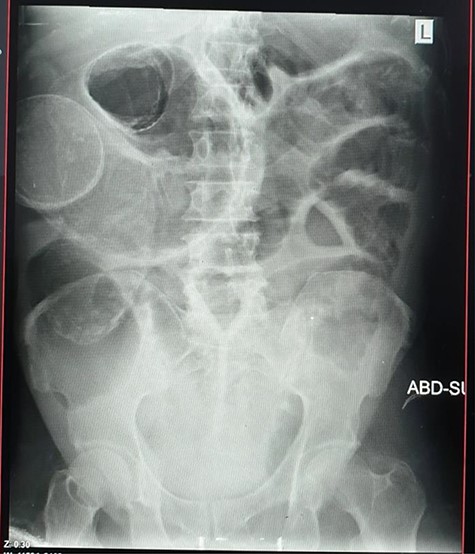

Plain abdominal X-ray (supine) showed grossly dilated large bowels (Fig. 1), and a chest X-ray showed a right-sided pneumothorax, which was managed by a thoracostomy tube (Fig. 2).

Chest X-ray showing right-sided pneumothorax with thoracostomy tube.